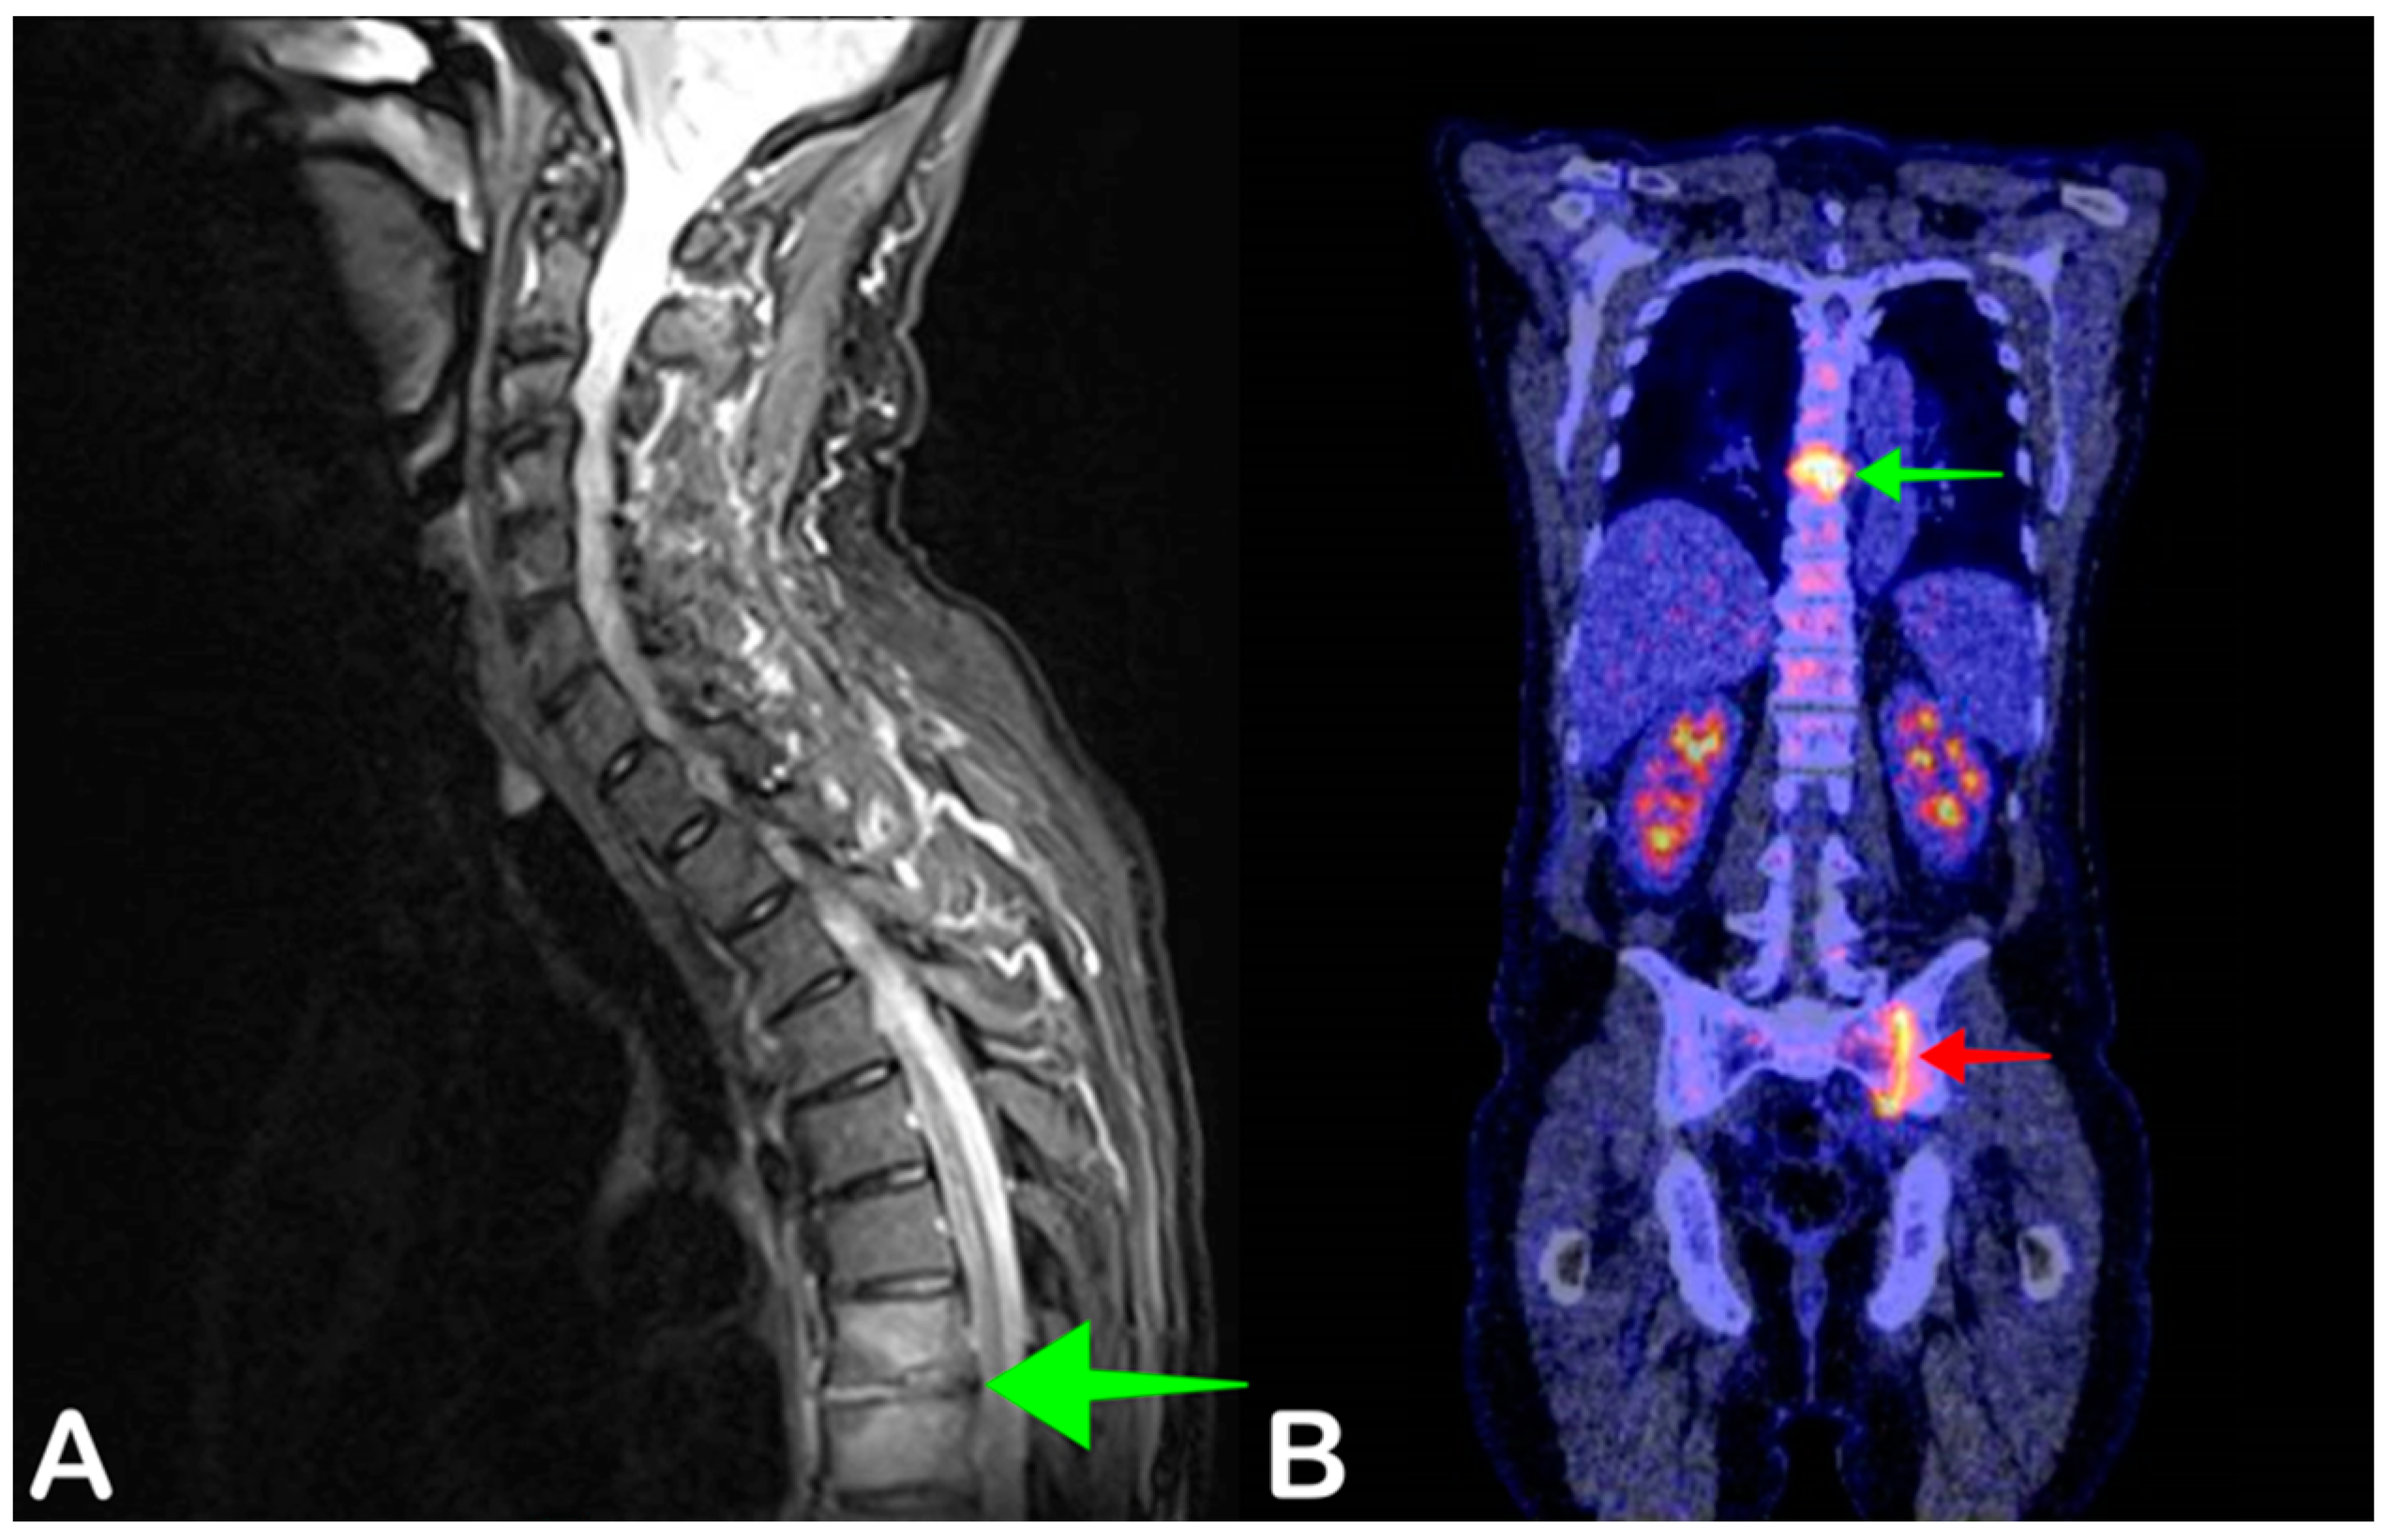

- Smids, C.; Kouijzer, I.J.E.; Vos, F.J.; Sprong, T.; Hosman, A.J.F.; De Rooy, J.W.J.; Aarntzen, E.H.J.G.; De Geus-Oei, L.-F.; Oyen, W.J.G.; Bleeker-Rovers, C.P. A comparison of the diagnostic value of MRI and 18F-FDG-PET/CT in suspected spondylodiscitis. Infection 2017, 45, 41–49. [Google Scholar] [CrossRef]

- Altini, C.; Lavelli, V.; Niccoli-Asabella, A.; Sardaro, A.; Branca, A.; Santo, G.; Ferrari, C.; Rubini, G. Comparison of the Diagnostic Value of MRI and Whole Body 18F-FDG PET/CT in Diagnosis of Spondylodiscitis. J. Clin. Med. 2020, 9, 1581. [Google Scholar] [CrossRef]